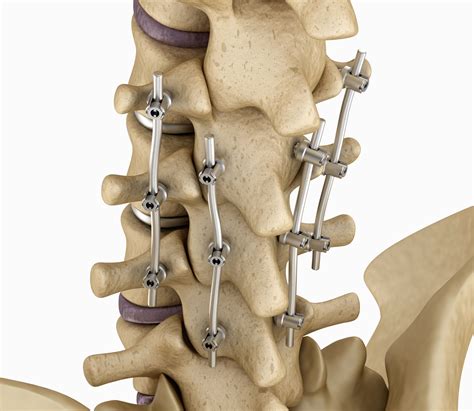

Posterior Lumbar Interbody Fusion (PLIF)

PLIF involves accessing the spine from the back and removing the damaged disc. The surgeon then inserts a bone graft or implant into the disc space to promote fusion. This procedure is often used for conditions like spondylolisthesis and degenerative disc disease.

• Stabilization: Additional hardware, such as screws, rods, or plates, may be used to stabilize the spine and promote fusion.